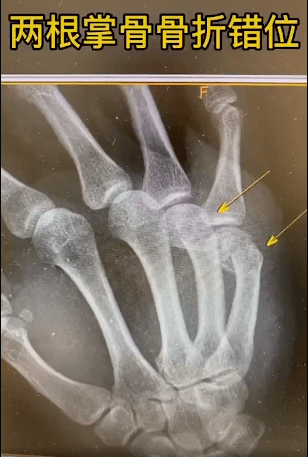

骨折似仰望图片,骨折图片

38种特殊骨折经典影像,你见过多少?

干货|这38种特殊骨折经典影像,建议收藏!

骨折x光片